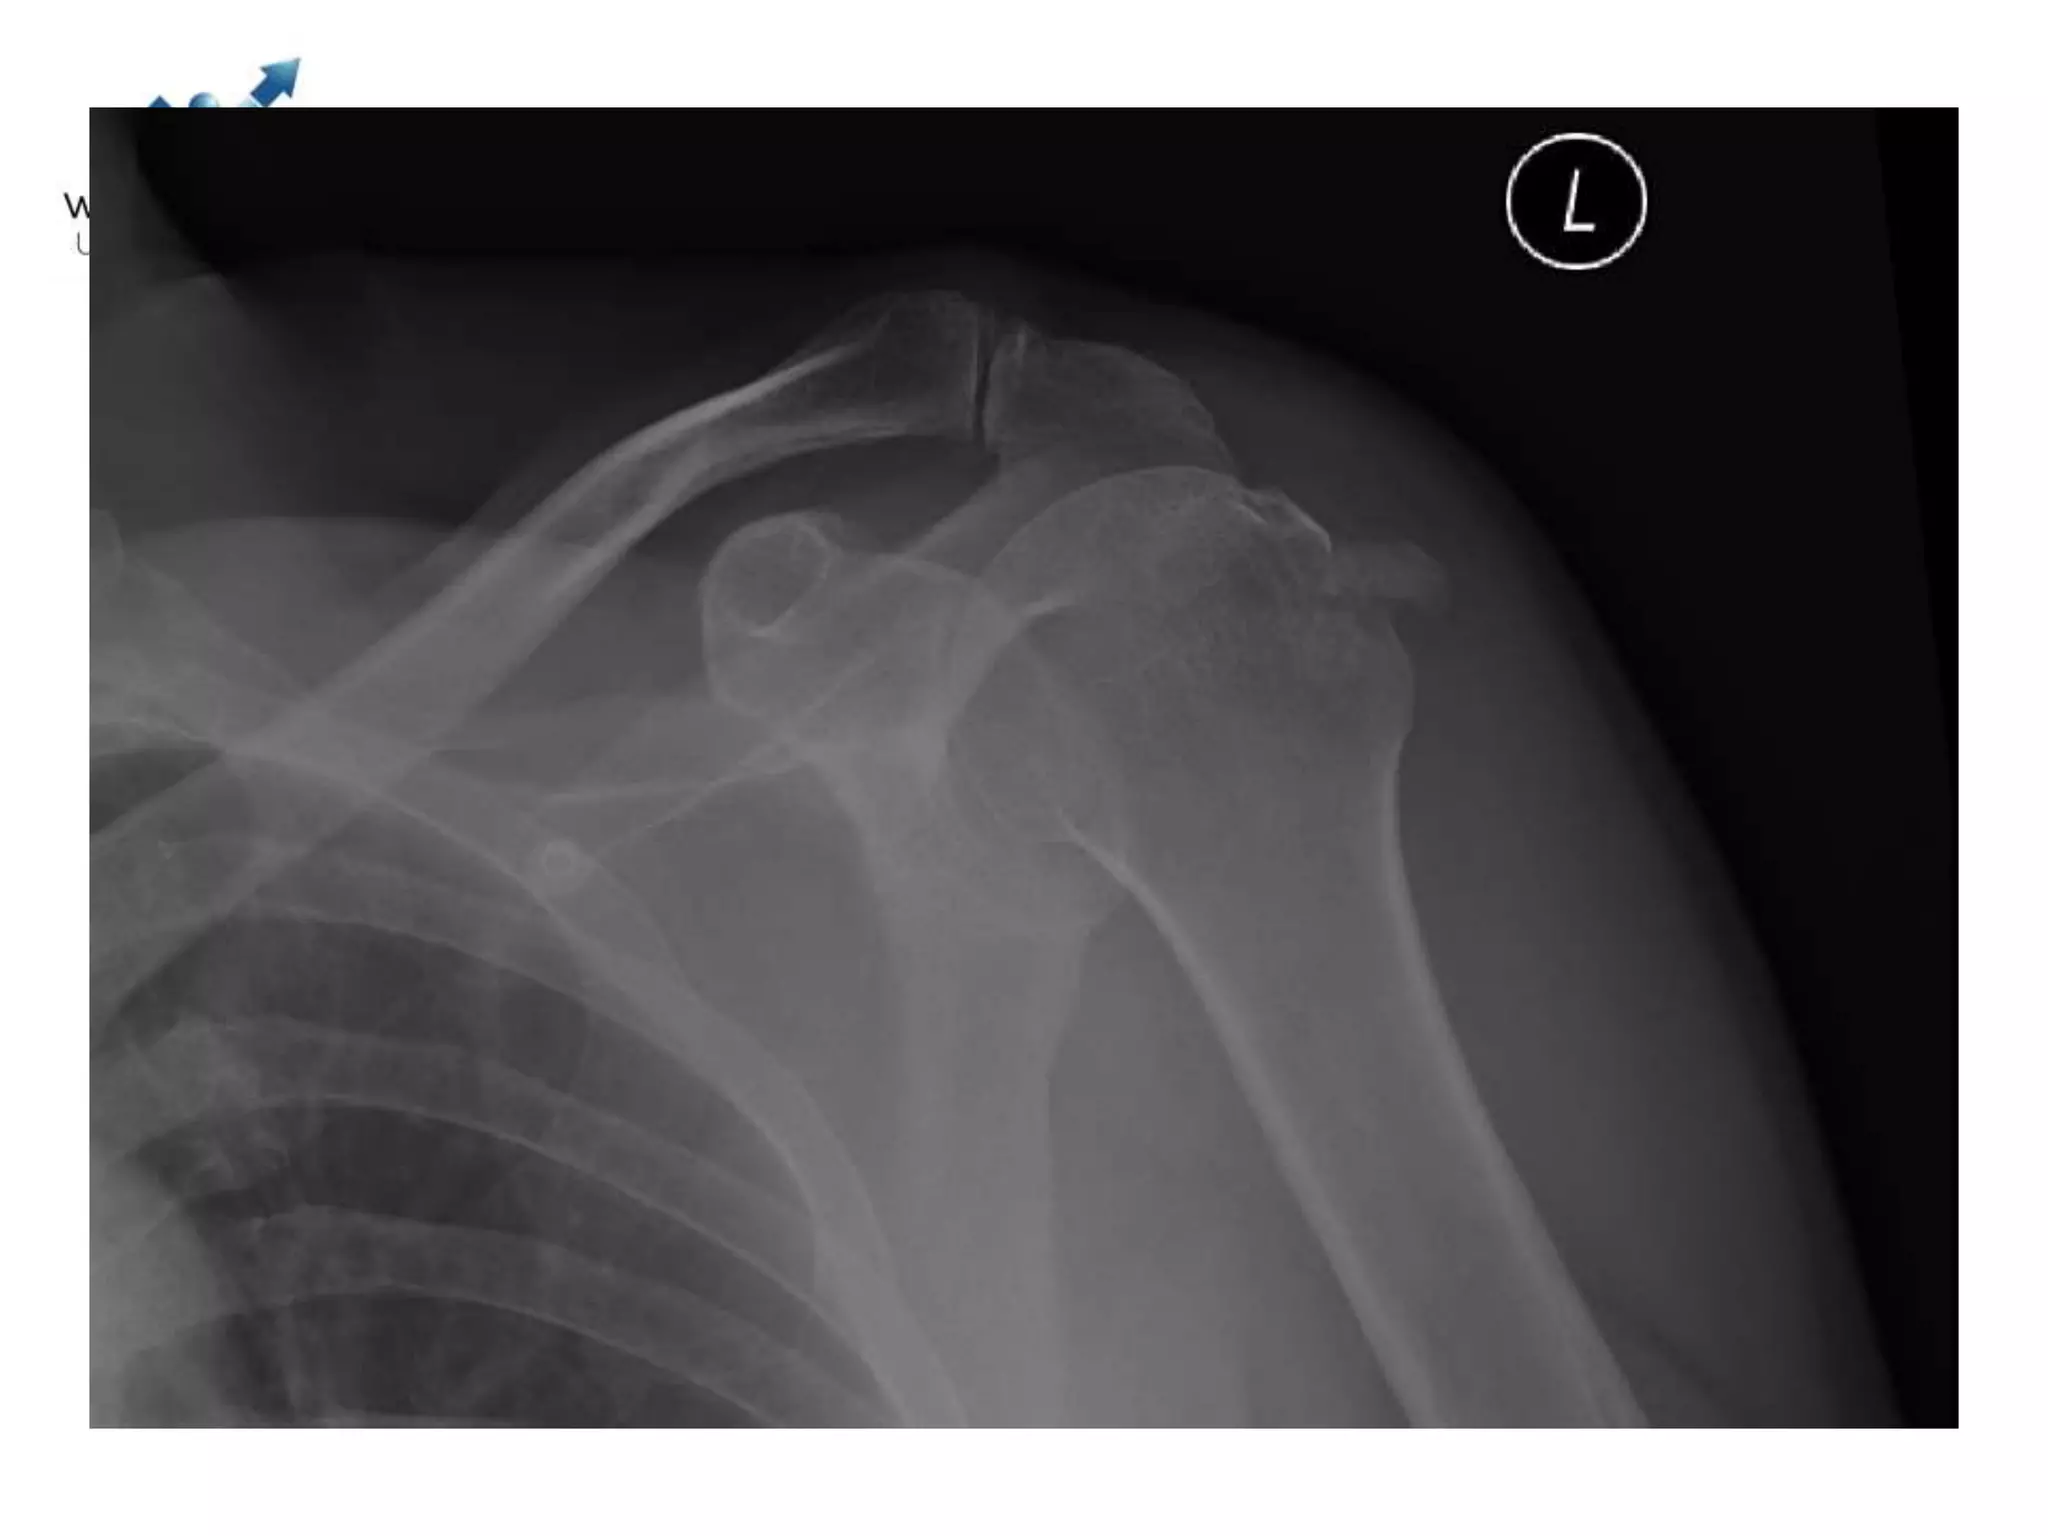

Case discussions

2 Next

3 Next